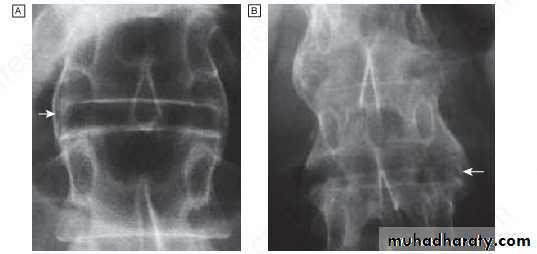

Radiographic changes in spondyloarthritis. A Fine symmetrical marginal syndesmophytes typical of ankylosing spondylitis (arrow).

B Coarse, asymmetrical non-marginal syndesmophytes typical of psoriatic spondylitis (arrow).